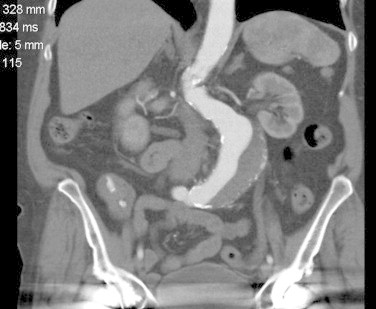

A 74-year-old woman, seen at another hospital for a 40 mm abdominal aortic aneurysm (AAA) one year earlier, presented to our vascular clinic. She complained of severe abdominal and back pain, which had lasted all day. Physical examination revealed a tender AAA. CT-angiography, demonstrated an infrarenal AAA with a diameter of 52 mm (Fig. 1, Fig. 4). Endovascular treatment with an Endurant® stentgraft was performed. Postoperatively, the patient initially was pain free. However, in the following days, she repeatedly experienced abdominal pain, now situated in the right lower quadrant. Review of the pre-operative CT-angiogram revealed a foreign body in the terminal ileum, which had been missed in the setting of a typical symptomatic AAA presentation. The patient could not remember having eaten anything unusual. During colonoscopy, the foreign body was seen inside the terminal ileum (Fig. 2, Fig. 5), and removal was attempted. Excessive pain was experienced during this attempt, raising concerns about possible perforation. Therefore, endoscopic retrieval was abandoned in favor of a laparotomy with enterotomy. In the terminal ileum, a plastic clip of the type normally used to close a bread bag was found (Fig. 6). The beak of the clip had attached itself to the mucosa of the small intestine (Fig. 3). Postoperatively, the patient had no abdominal complaints.

Fig. 1.

CT-image of AAA and foreign body.

Fig. 4.